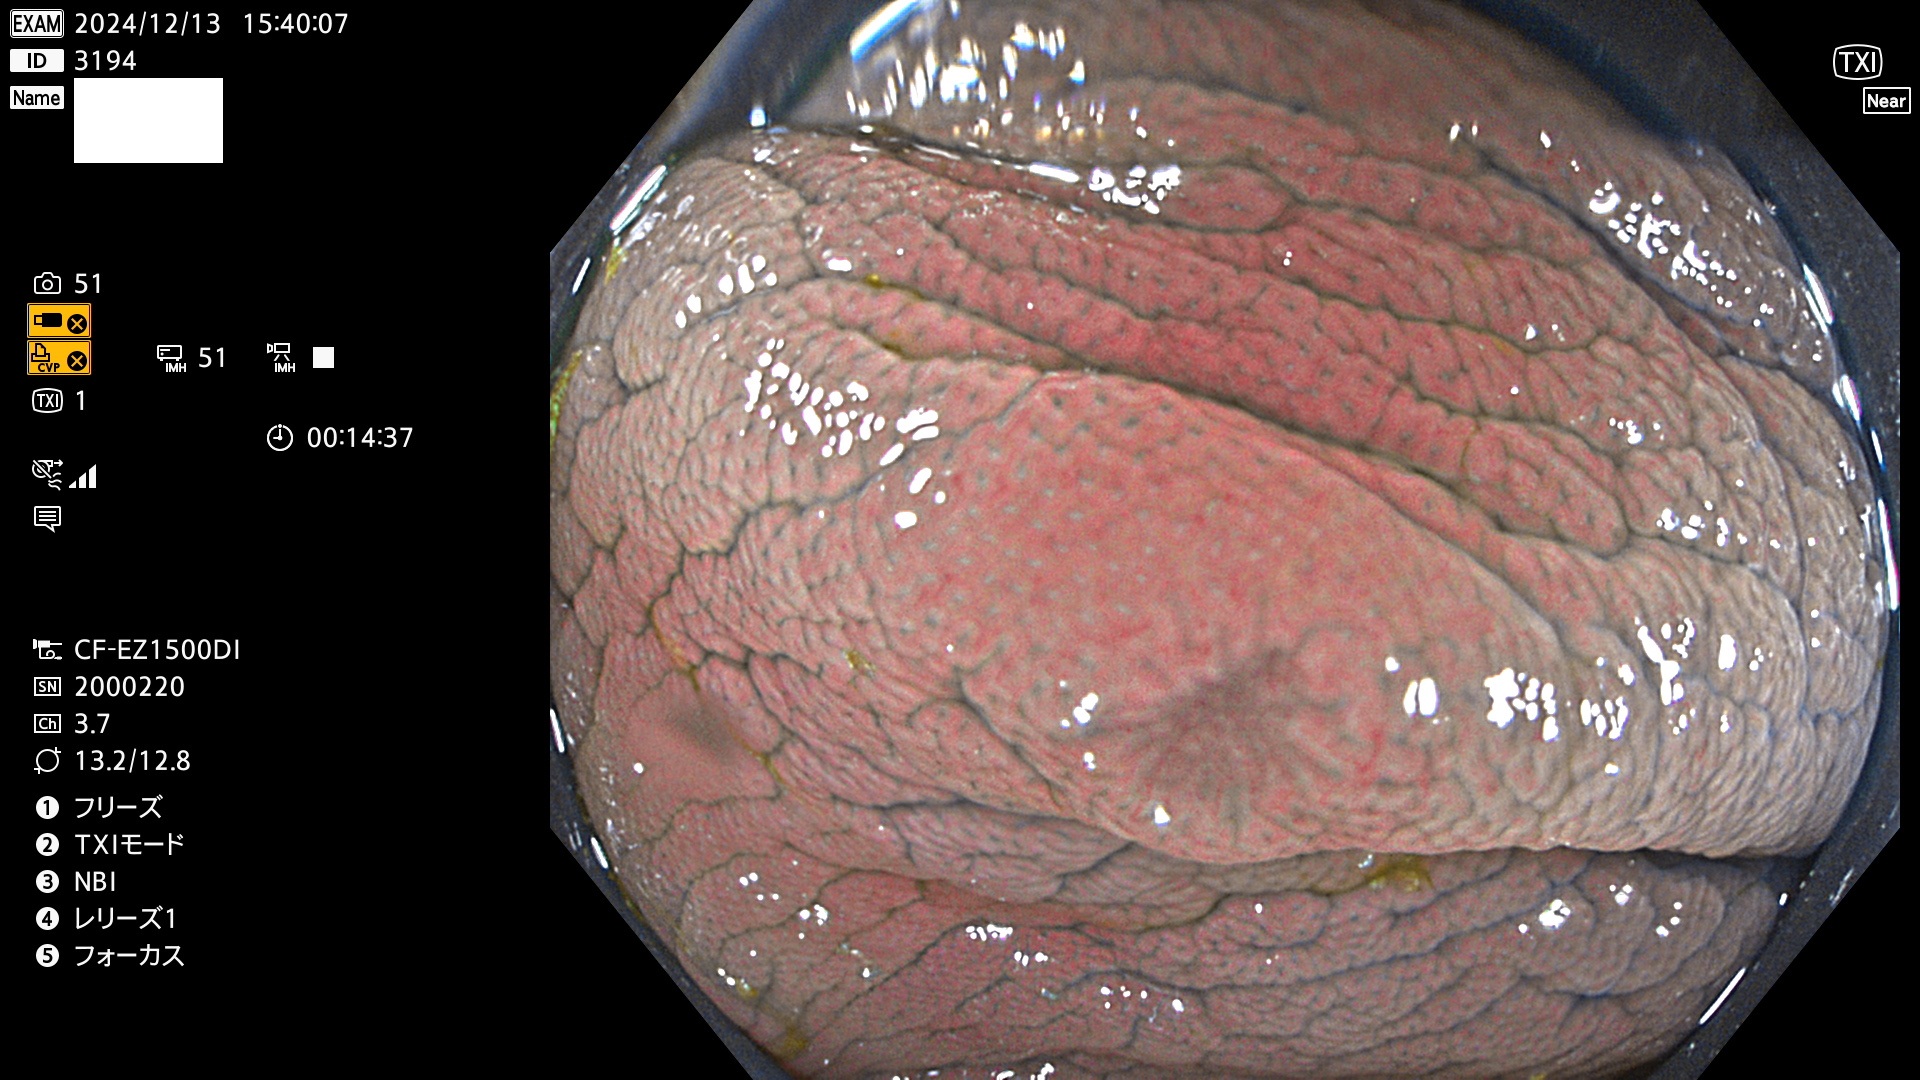

完全に平坦な物をUb、陥凹している物をUcと呼びます。最も発見が難しく危険な病変です。

毎週の検査(木・金・土・日)に発見されたUb、Uc型・腺腫を、その週の日曜の夜にUPし1週間、提示します。

抽出の対象期間 2024年12月12日〜12月16日の5日間(60件の検査)13件 (13/60=21%)